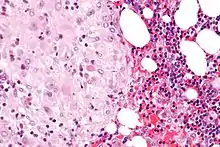

The decidua has a histologically-distinct appearance, displaying large polygonal decidual cells in the stroma. These are enlarged endometrial stromal cells, which resemble epithelium (and are referred to as "epithelioid").

Acute choriodeciduitis, with neutrophils seen in the chorion and decidua.

Acute choriodeciduitis, with neutrophils seen in the chorion and decidua.